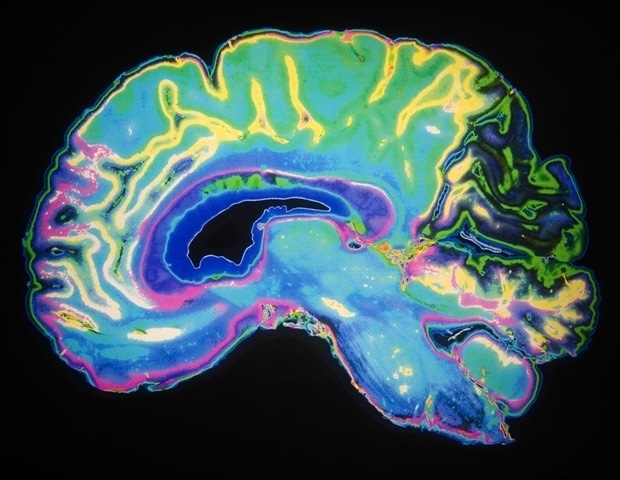

Psychiatric disorders affect millions worldwide, but their diagnosis still relies on clinical observation instead of standard biological tests. In an attempt to identify reliable biomarkers, scientists in China have now launched the Brain-Gut Health Initiative, a large-scale longitudinal study combi…